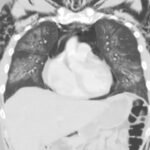

Electronic cigarette (e-cigarette) or vaping associated lung injury (EVALI) cases have increased with the popularity of e-cigarettes in the mostly young, healthy population. Some common symptoms associated with EVALI include shortness of breath and chest pain, and the most common diagnostic imaging findings are organizing pneumonia and diffuse alveolar damage seen on computed tomography (CT). Pneumomediastinum is a known sequela of EVALI.1 In the setting of pneumomediastinum in EVALI, EVALI is a diagnosis of exclusion, so other sources of pneumomediastinum need to be evaluated. EVALI has diverse presentations, and this case is a unique representation of a disease process that is becoming more commonplace with the increase in popularity of vaping. It is important to be aware of the clinical symptoms of EVALI, which can be nonspecific and can include gastrointestinal symptoms along with respiratory symptoms. It is equally important to recognize the diverse image findings of EVALI, which can include subcutaneous emphysema and pneumomediastinum. In this case, pneumomediastinum is seen in EVALI, and the patient was successfully treated with empiric antibiotic coverage, steroids, and conservative measures—making sure to limit any coughing or increases in intrathoracic pressure that can cause worsening of pneumomediastinum.